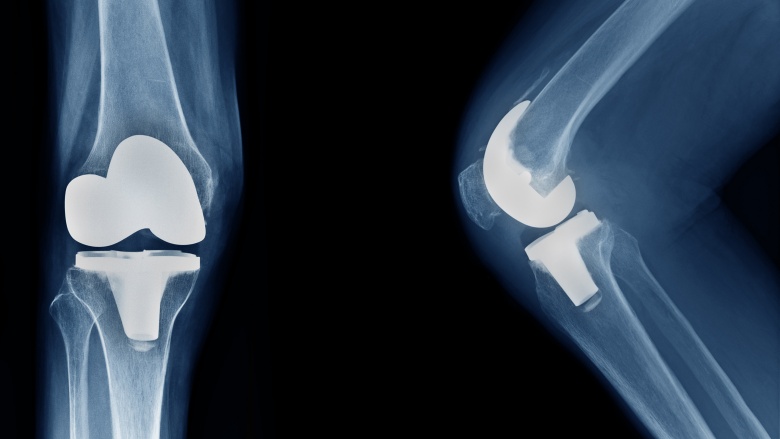

There will be less strain on your joints

People who lose a lot of weight may find they have fewer aches and pains throughout the day, and this can largely be attributed to their joints. In addition to muscles and ligaments, our joints help hold us up when we stand and move. Many of these joints also support the weight we carry. These weight-bearing joints include the knees, hips, and ankles for primary support. When you carry extra weight, these joints have to offer more support. While everyone experiences wear and tear on their weight-bearing joints over time, those who are overweight or obese experience much more wear and tear over time. This leads to a higher prevalence of not only general joint pain, but also osteoarthritis and joint replacement.

Research has shown that not only will losing weight decrease the chance you'll develop arthritis, losing weight can also help improve your symptoms if you have already been diagnosed with arthritis. A 2005 study found that a weight-loss of just five percent (ten pounds for a woman starting out at 200 pounds) brought about an average 18 percent improvement in osteoarthritis symptoms, including reduced pain and improved joint function. Another study the same year showed that a weight reduction of ten percent (20 pounds in the same 200 pound woman) resulted in a 28 percent improvement in joint function. This suggests that the more weight you lose, the more joint function improvement you will see, whether or not you have been diagnosed with osteoarthritis.